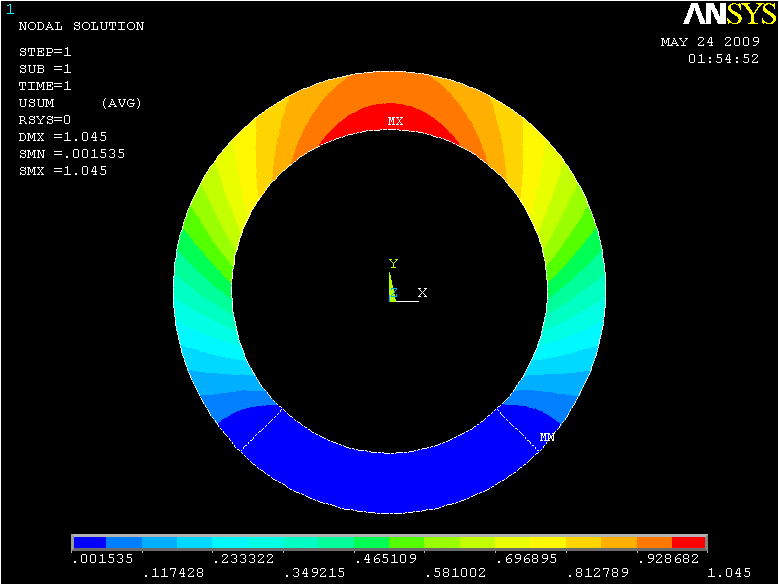

In case of plane strain, the problem at hand can be simplified as follows. Assume that we have an inhomogeneous ring cylinder with a known height. Since the foundation of our research is based on the assumption of plain strain/stress, there is no strain/stress along the direction and therefore the cylinder’s height doesn’t have any effect on the solution. The assumption of an inhomogeneous ring cylinder is because of the changes occurred in the mechanical properties of heart muscle after introducing infarction. After defining the elastic properties of the ring cylinder, the structure is ready for the next step which is loading. In this step the load is applied in a uniform and radial manner inside the ring, to mimic the process of loading the heart muscle. The internal pressure applied to the ring is time varying. Fig.3 represents the results of ANSYS analysis of the ring for displacement in , and the absolute values of displacements respectively.

Fig. 4 represent the results of the proposed method for both horizontal, vertical and absolute displacement. To better be able to compare the results, the ring is divided into 16 sub-regions and the results of ANSYS and MATLAB implementations are compared. Fig. 5 shows the average displacement in each region for 10 iterations of pressure increment for both ANSYS and proposed method. Based on the provided results, it can be seen that the proposed model is consistent with the results of ANSYS, even in regions with low mobility (regions 11, 12, 13 and 14).